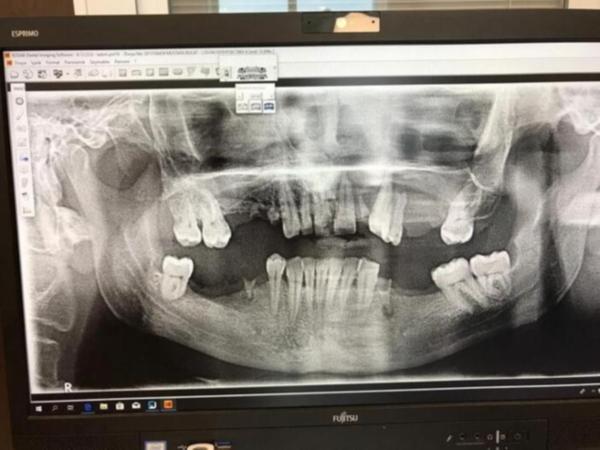

Avukat Neslihan Güraslan ise diş hekiminin tetkik yapmadan, ilaç kullandırtmadan dişi çekmesinin ihmalkarlık olduğunu söyleyerek, “Müvekkilim bir diş ağrısı sebebiyle ağız ve diş sağlığı merkezine gidiyor. Doktor müvekkilimin yüzünde şişlik olduğu halde herhangi bir tetkik veya bir ilaç kullanımı tavsiye etmeden direk müvekkilimin dişini o gün, gittiği gün çekiyor. Bunun üzerine müvekkilimin yüzüne bütün iltihap yayılıyor ve bundan sonrasında da müvekkilim ameliyat olarak maalesef sol gözünü ve yüzünün sol tarafını kaybediyor. Zaten müvekkilimin görüntülerinde de gördüğünüz üzere maalesef büyük bir mağduriyet yaşanıyor. Müvekkilim de evli ve iki çocuk babası. Biz burada ihmal olduğunu düşünüyoruz. Diş hekiminin burada gerekli özen ve hassasiyeti göstermediğini düşünüyoruz. Zaten bununla ilgili yargı sürecini başlattık, gerekli şikayetleri yaptık, durum şu anda yargıda” dedi.

“Bu adı geçen hasta ilk olarak hastanemize 28 Mart 2019’da başvuruyor, bir hekim arkadaşımız hastaya müdahale ediyor ve bu hastaya ilaç yazılıp gönderiliyor. Bu hasta arkadaşımız Nisan’ın 3’ünde tekrar hastanemize başvuruyor. Yine bana değil başka bir hekim arkadaşa gidiyor. Bu hekim arkadaşımız sol üst tarafından 3 tane diş çekiyor. En son bize de Mayıs’ın 16’sında geliyor. Kapıdan girer girmez hastayı gördüğümüzde gözü tamamen şişti. Ağzına baktığımızda sol üst çenesi tamamen erimiş ve damar ağız içinde sarkık vaziyetteydi. Hemen yanında gelen babasına da 'amca siz burada ne geziyorsunuz, bu çocuğu bir an evvel fakülteye götürmen gerekiyor.' Babası da bize dert yandı, oğlum gitmiyor, ilaçlarla geçeceğini sanıyor. Biz hastanın bir üst kurul olan üniversiteye gitmesi gerektiğini anlattık. O sırada hasta rahat etsin diye önde sallanan kök olarak erimiş, sol üst 1 numaralı dişi elimizle aldık. Çünkü artık kemik erimiş, diş eti ağız içerisinde sallanıyor ve sol gözünü artık kaybetmek üzere olduğunun teşhisini koymuştuk.”

Hastanın ve ailesinin derdinin para koparmak olduğunu ileri süren A.P. “Aileye bize de bilgi verin dedik. Aradan 15 gün geçti bilgi alamayınca, ben kendi telefonumdan arayarak bilgi istedim. Ayrıca şayet çekilen diş sonucu bu olay yaşansa bile biz o bölgeden diş çekmedik daha önce çekilmiş zaten, röntgende de var bunlar. Bu olay iltihaplık diş çekimiyle olan bir olay değil. Bunların amacı yönlendirme ile hekimi tacizle para koparmak, biz bunu anladık. Biz teşekkür beklerken bu tepkilere maruz kaldık” ifadelerini kullandı.